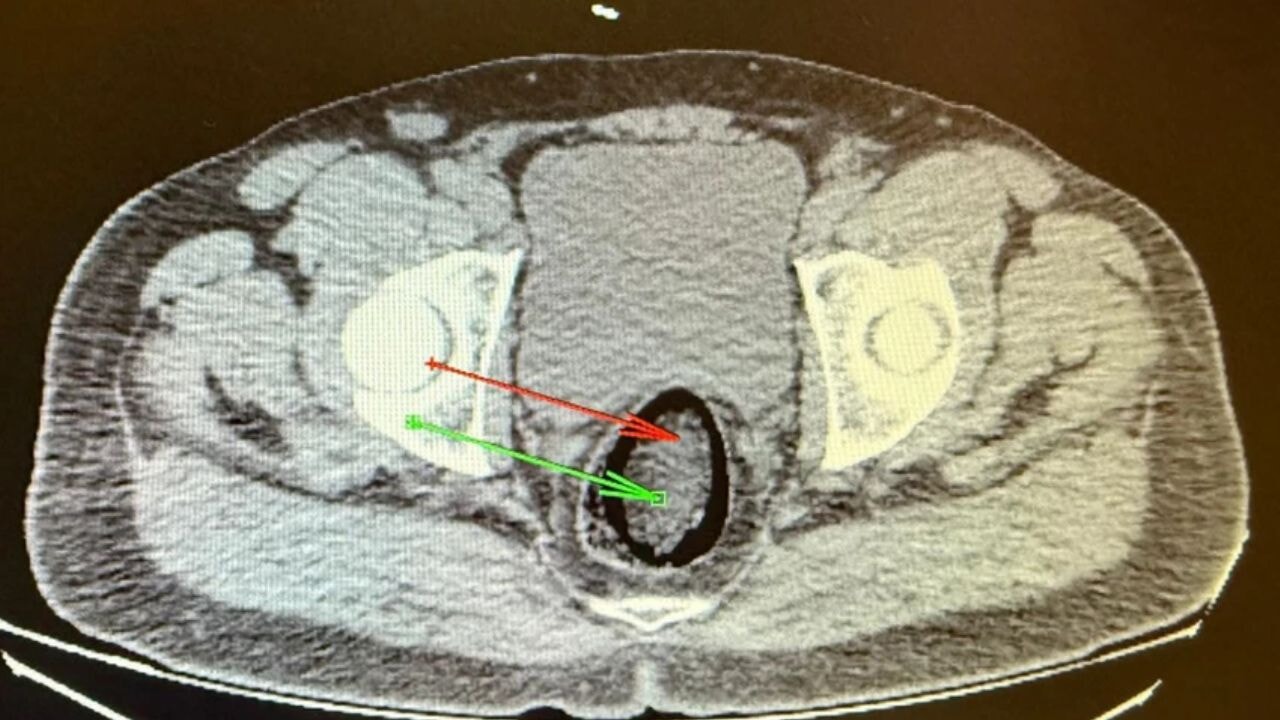

Kars'ta polisin yol kontrolü sırasında durdurduğu yolcu otobüsünde, hareketlerinden şüphelenilen İran uyruklu F.H. adlı yolcunun üzerinde yapılan kontroller sonrası, makatına sakladığı uyuşturucu tespit edildi. Kars Harakani Devlet Hastanesi'nde çekilen röntgende ortaya çıkan uyuşturucu madde, cerrahi operasyonla çıkarıldı. Zanlı, çıkarıldığı mahkemece tutuklanarak cezaevine gönderildi.

Harakani Devlet Hastanesi'nde yapılan taramalarda, şahsın makatında yabancı cisim olduğu belirlendi. Yapılan cerrahi müdahale sonucunda, 105,98 gram metamfetamin ele geçirildi. Ele geçirilen uyuşturucu maddenin piyasaya sürülmek üzere Türkiye'ye sokulmak istendiği değerlendiriliyor.